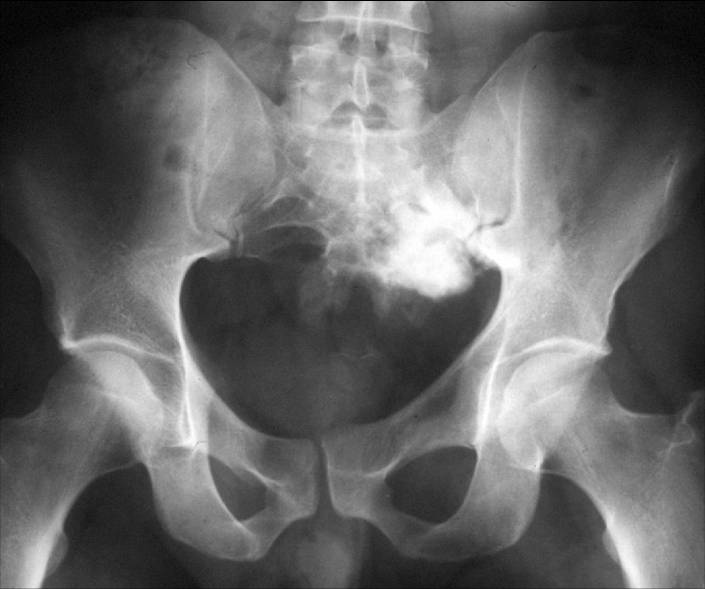

Саркома тазобедренной кости

Саркома тазобедренной кости — довольно редкое онкологическое заболевание, проявляющееся в образовании опухоли в области костной ткани.

Опухоль может возникать как из костной ткани (тогда говорят об остеосаркоме) или из хрящевой ткани (тогда имеет место хондросаркома).

Чаще всего эту патологию ошибочно называют раком тазобедренной кости. Это неверно, поскольку в теле человека нет такой области: тазовая и бедренная кость в месте их соединения и образуют тазобедренный сустав).

Симптомы саркомы тазовой кости

Эта патология на начальных порах отличается еще и скрытыми симптомами, которые легко перепутать с другими болезнями и воспалениями.

Это часто возникающие боли в области таза или ягодиц, повышение температуры тела. Как видно, признаки эти неуникальны и проявляются при множестве других болезней.

Поэтому выявить именно онкологию можно, пройдя специальное обследование с использованием медицинского оборудования.

И только когда саркома тазовой кости уже развилась достаточно, на коже пациент может обнаруживать выступы, утончение кожного покрова, пятна (на языке хирургов — сосудистый рисунок).

И только с помощью диагностики и специального оборудования можно выявить саркому кости: будет видно, как раковая опухоль сдавливает внутренние органы, пережимает сосуды и нервы.

Именно это является причиной возникновения сильной боли, которая даже может распространяться в бедро, половые органы и т. д.